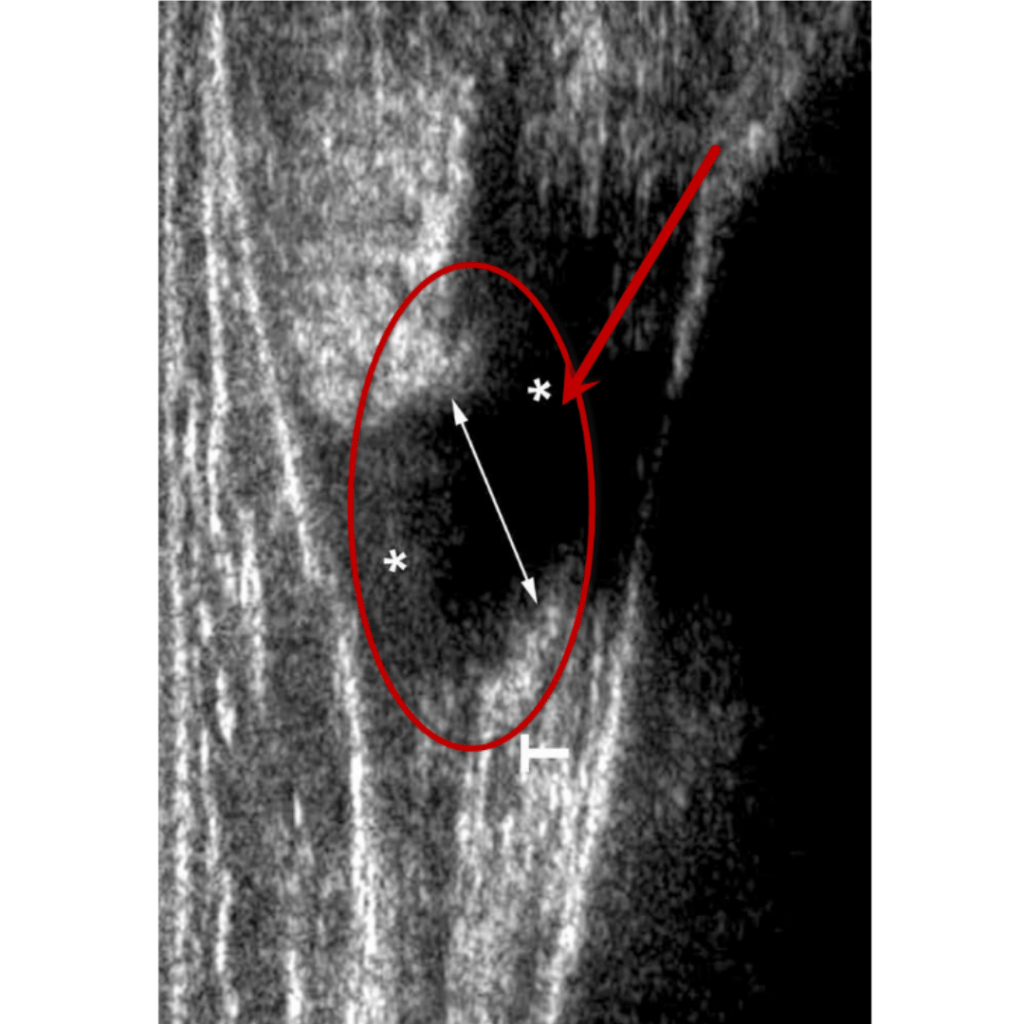

El diagnóstico de esta afectación dependerá mucho de su localización, en caso de sospecha de compromiso en un músculo superficial se puede hacer uso de ecografía (ultrasonido), en tejidos más profundos es más eficiente una resonancia magnética.

Ultrasonido

Ruptura total Grado III